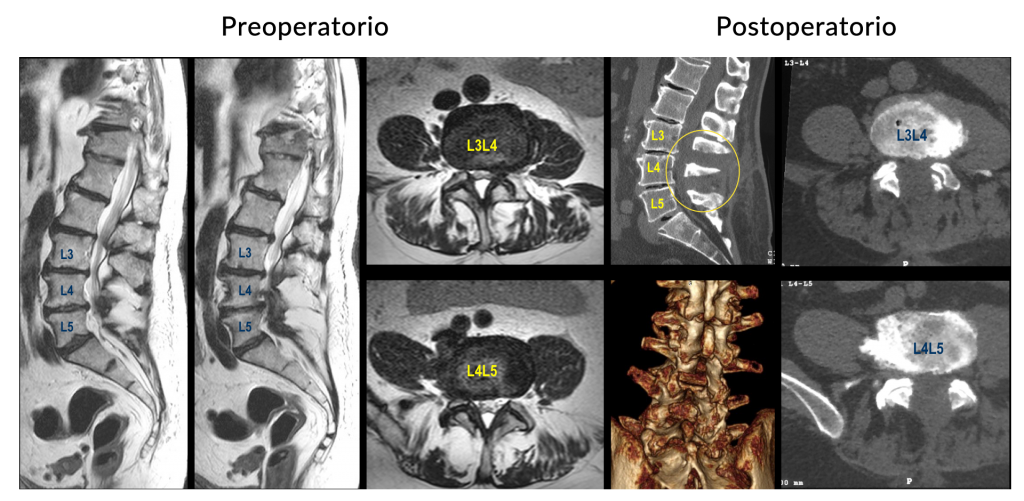

Hernia de

disco lumbar